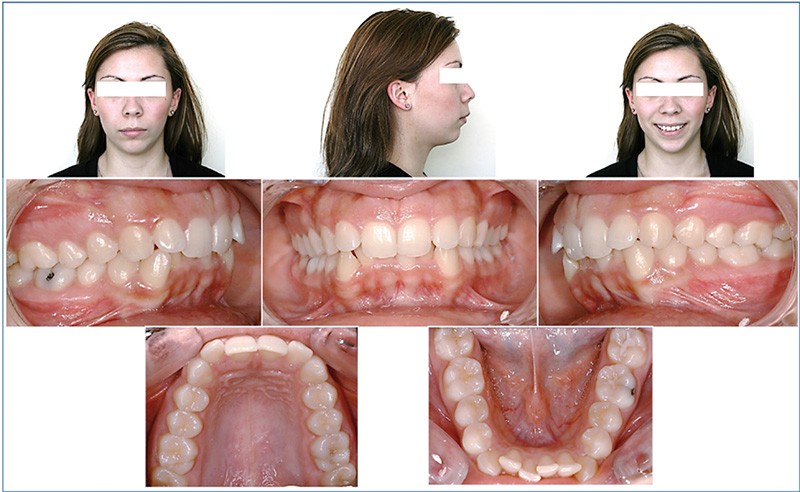

Esthétique : diminuer la convexité du profil et harmoniser le sourire.

Squelettique : corriger la rétromandibulie et obtenir une classe I de Ballard.

Dentaire : corriger la DDM, vestibuloverser les incisives maxillaires, corriger la supraclusion et conserver la classe I d’Angle.

Fonctionnel : rétablir un guide antérieur fonctionnel.